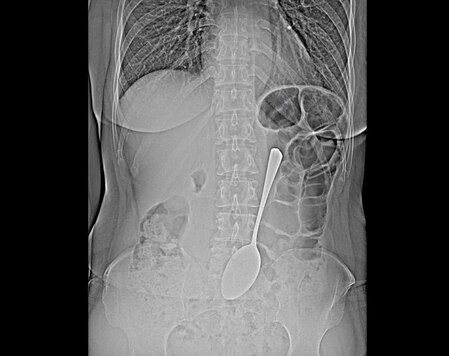

Жительница Бурятии проглотила ложку длиной 18 см

Врачи БСМП в Улан-Удэ спасли женщину, которая проглотила столовую ложку длиной 18 см.

Ложку эндоскописты достали из желудка с помощью эндоскопа и соответствующих инструментов, что помогло избежать сложной хирургической операции.

«Инородные предметы в желудке могут спровоцировать перфорацию желудка, кишечную непроходимость. Если мелкие предметы вроде монет могут выйти из организма самостоятельно, то в случае со столовой ложкой все могло быть серьёзнее», - прокомментировал врач-эндоскопист БСМП имени Ангапова Валентина Бабудоржиева.

После проведённой процедуры женщину отпустили. Каким образом она сумела проглотить ложку, она так и не рассказала.